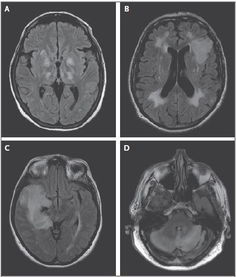

急性病毒性腦炎(其它),病毒性腦炎是指病毒直接侵犯腦實質(zhì)而引起的原發(fā)性腦炎(由節(jié)肢動物傳播的流行性腦炎以及變應性腦炎,接種后腦炎不在本文范圍內(nèi))。

本病一年四季均有發(fā)生,故又稱散發(fā)性腦炎。引起腦炎常見的病毒有腸道病毒、單純皰疹病毒、粘液病毒和其他一些病毒。

臨床上主要表現(xiàn)為腦實質(zhì)損害的癥狀和顱內(nèi)高壓征,如發(fā)熱、頭痛、嘔吐、抽搐,嚴重者出現(xiàn)昏迷。但由于病毒侵犯的部位和范圍不同,病情可輕重不一,形式亦多樣。

有的病兒表現(xiàn)為精神改變,如整天想睡,精神差,或亂吵亂叫,或不省人事;有的則出現(xiàn)手、腳癱瘓。也由于感染的病毒的種類不同,臨床表現(xiàn)亦有輕有重,預后也各異。